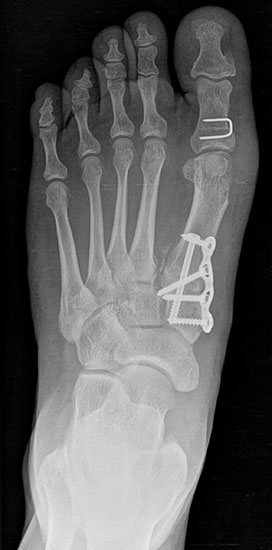

Bezüglich der Operationstechniken wird von früher häufig durchgeführten alleinigen Weich­teileingriffen am Großzehengrundgelenk aufgrund hoher Rezidivraten abgeraten 15. Die Operation nach Mc Bride mit lateralem Release, Exzision des lateralen Sesambeins, Abtragen der Pseudoexostose, Sehnenetransfer des M. adductor hallucis und mediale Kapselraffung zeigte unbefriedigende Mittel- und Langzeitergebnisse 16. Die Cerclage fibreux (mediale Kapselraffung) und das laterale Kapselrelease wird heute in Kombination mit einem knöchernen Eingriff angewendet. Bezüglich des Einsatzes von minimalinvasiven Operations­techniken vor Wachstumsabschluss liegen bisher keine Daten vor. Alle Osteotomien lassen sich nach Bedarf miteinander kombinieren. Es ist darauf zu achten, dass Osteotomien keine offenen Wachstumsfugen verletzen.

• Medial zuklappende Grundphalanxosteotomie nach Akin 17

• Subcapitale distale Chevron Osteotomie nach Austin 18

• Diaphysäre Osteotomie

• Scarf 19

• Ludloff 20

• Proximale Metatarsale I Osteotomien 21

• medial aufklappend – verlängernd

• lateral zuklappend – verkürzend

• bogenförmige Crescentic Osteotomie

• proximale Chevron Osteotomie

• proximale Verschiebeosteotomie

• medial aufklappende Cuneiforme I Osteotomie 1522

• Wachstumslenkung: Hemiepiphysiodese der lateralen Basisfuge am Metatarsale I  23

• Nach Schluss der Wachstumsfugen: TMT I Arthrodese nach Lapidus 2425